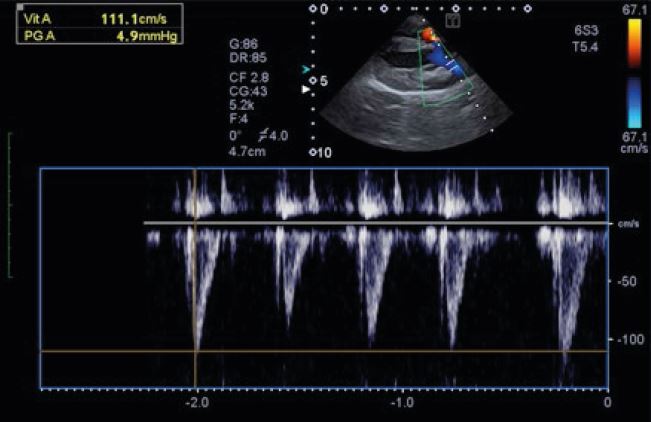

Кардіологічне дослідження у собаки в імпульснохвильовому

доплерівському режимі, що відображає аортальний потік.